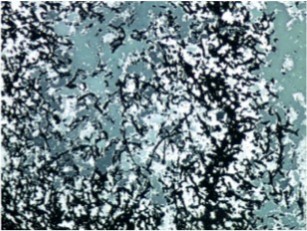

Figure 4.Light Green PAS stain with filamentous branching bacteria at 10x magnification